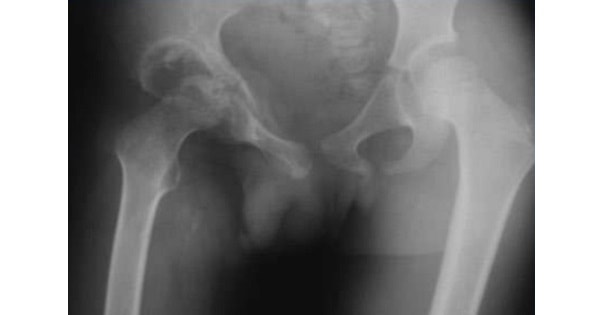

TUBERCULOSIS OF HIP

- Presentation is with hip pain or limp. The limb is in attitude of slight flexion, abduction and external rotation. The child may have low grade fever. The ESR, C-Reactive protein & WBCs count are normal (This differentiates Transient synovitis from Septic arthiritis a serious condition, in which patient has high grade fever and elevated ESR, C-Reactive protein and WBC count). Radiograph or ultrasound may show widening of the joint space However, most of the time x-ray is normal.